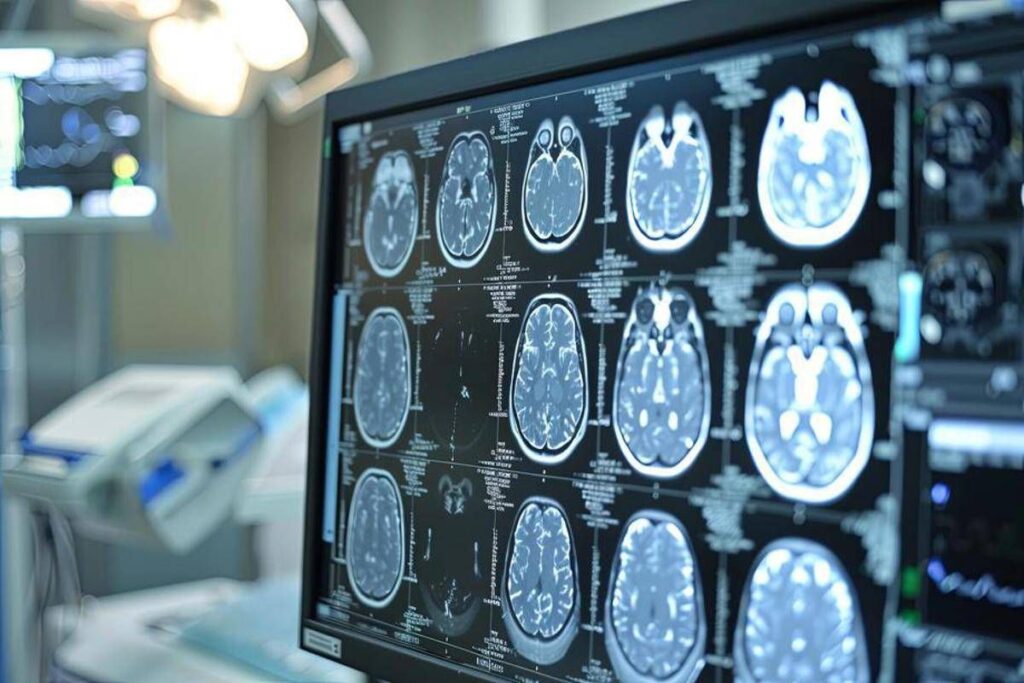

Lo Spoke viene così riconosciuto non come struttura “accessoria”, ma come elemento strategico del sistema, capace di trasformare la rete da concetto teorico a infrastruttura clinica funzionante. “Le malattie rare rappresentano una sfida clinica in continua evoluzione – ha sottolineato Maria Paola Campisi, dirigente medico Uoc Cardiologia P.O. Ingrassia Asp Palermo – Si tratta di un gruppo eterogeneo di patologie che, se non correttamente inquadrate e gestite, hanno un impatto significativo sulla morbilità e mortalità. Da qui l’importanza di creare una rete attraverso il ruolo dei centri Hub e Spoke sul territorio siciliano per garantire un accesso equo e tempestivo a tutti gli strumenti diagnostici avanzati (RMN, Medicina Nucleare, Genetica). Strategie concrete per la Sinergia tra Ospedale-territorio e la sostenibilità farmacologica per dare beneficio a tutti i nostri pazienti che convivono con queste patologie ancora oggi sotto diagnosticate”.